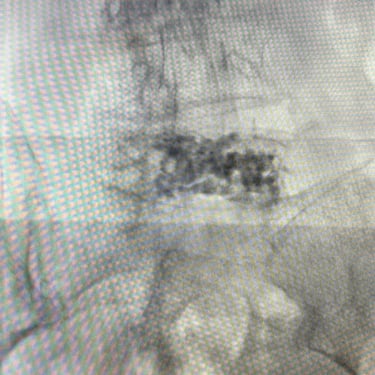

🧠Fractura vertebral lumbar osteoporótica en el adulto mayor: manejo con vertebroplastia percutánea.

Las fracturas vertebrales osteoporóticas en adultos mayores son una causa frecuente de dolor lumbar incapacitante. La vertebroplastia percutánea es un procedimiento mínimamente invasivo que permite estabilizar la vértebra afectada mediante la inyección de cemento óseo, logrando alivio del dolor y recuperación funcional temprana en pacientes seleccionados.